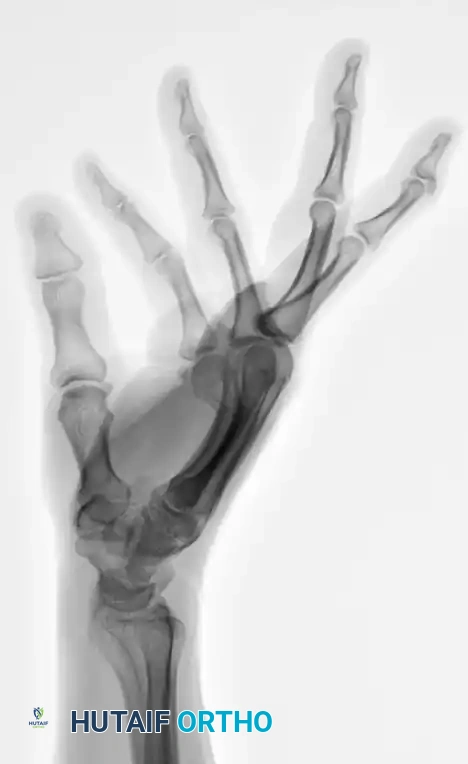

FIGURE 67-35C: Preoperative lateral radiograph showing 80-degree apex dorsal angulation and rotational deformity.

FIGURE 67-37C: Postoperative AP radiograph showing intramedullary fixation with a Kirschner wire.

FIGURE 67-37D: Postoperative lateral radiograph confirming anatomic restoration.